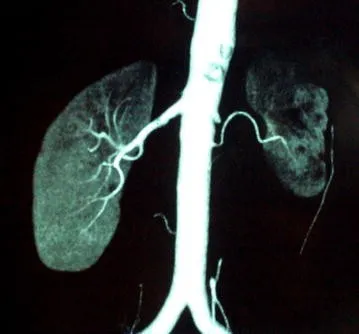

DRPAD além do Tolvaptana: Novas Perspectivas Terapêuticas nas Diretrizes KDIGO 2025

Além do tolvaptana, as diretrizes KDIGO destacam a importância de medidas não farmacológicas e abordagens complementares no manejo da DRPAD, como controle rigoroso da pressão arterial, redução de ingesta de sal e aumento de ingestão hídrica. Estudos em andamento também avaliam terapias-alvo envolvendo vias do mTOR, cAMP e inflamação. O manejo multidisciplinar permanece essencial para retardar a progressão da doença e melhorar a qualidade de vida.

Uso do Tolvaptan na DRPAD: O Que falam nas Novas Diretrizes KDIGO 2025?

As novas diretrizes KDIGO para a Doença Renal Policística Autossômica Dominante (DRPAD) atualizam os critérios de elegibilidade para o uso de tolvaptana, com ênfase na estratificação do risco de progressão rápida. O documento reforça a individualização da terapia com base em subclassificação por imagem (Mayo Clinic) e função renal. A incorporação prática dessas recomendações pode otimizar o manejo e retardar a progressão da DRC nesses pacientes.